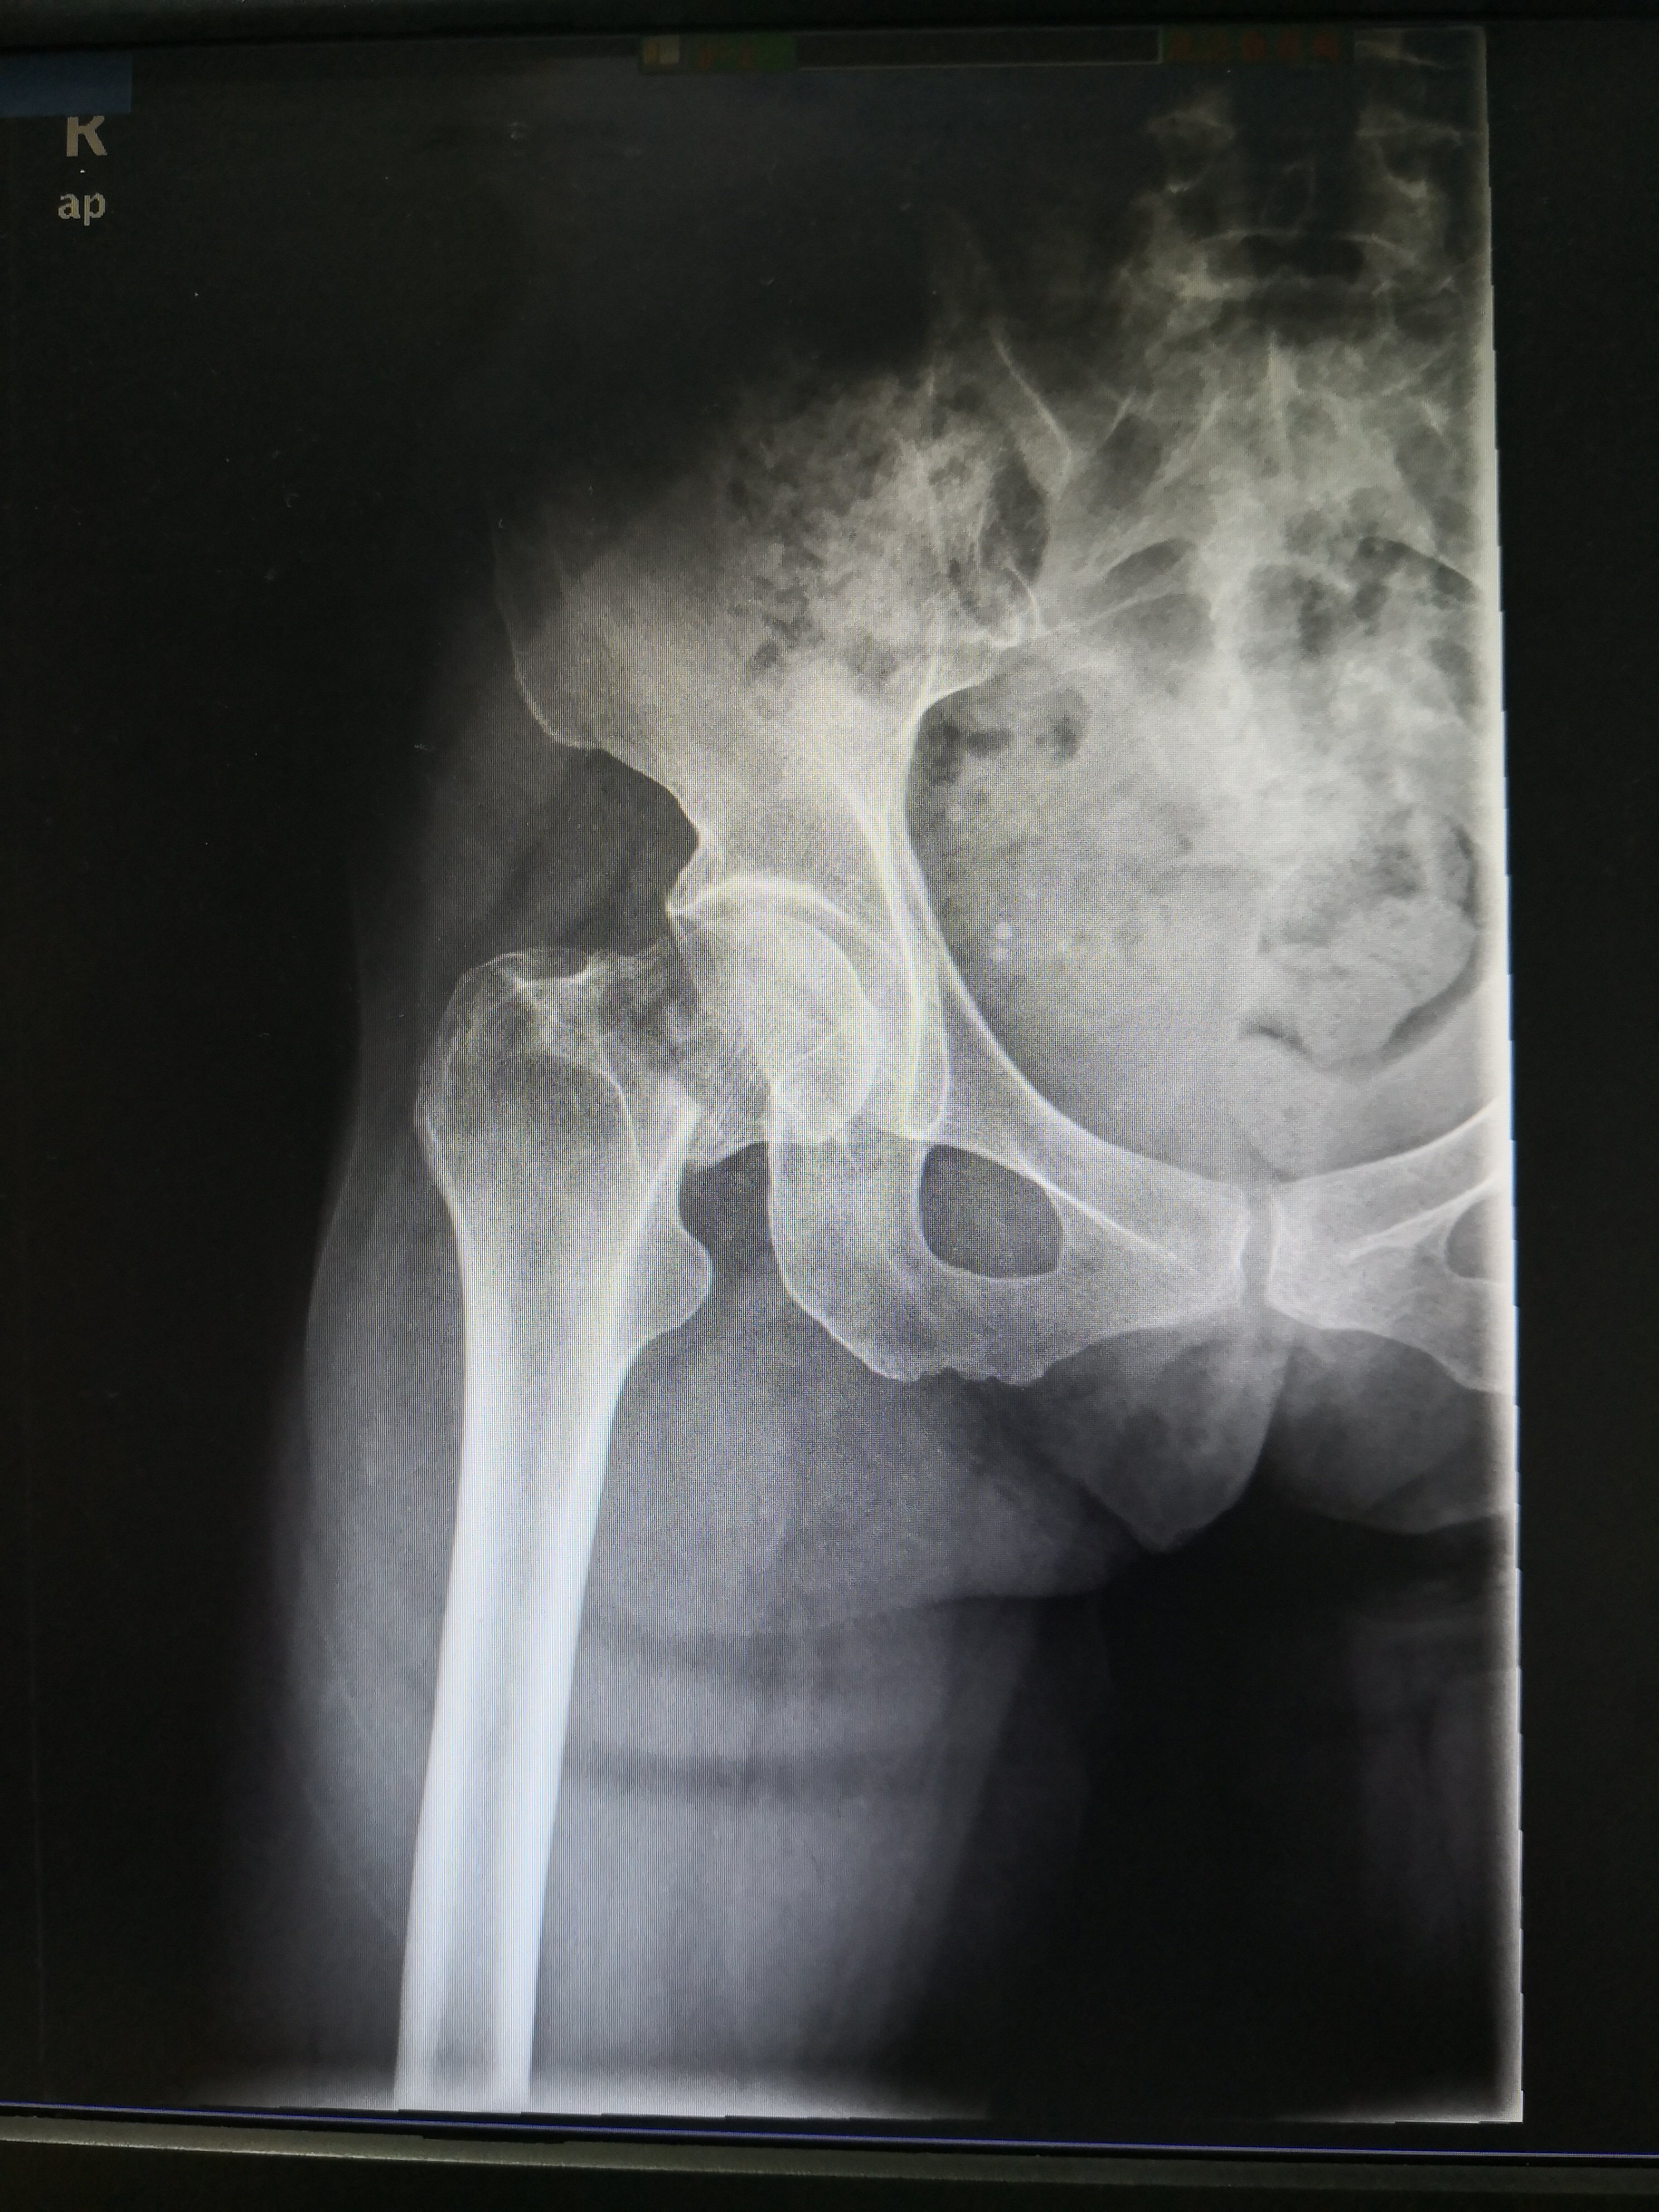

术前股骨颈骨折

IMG_20190323_184542.jpg